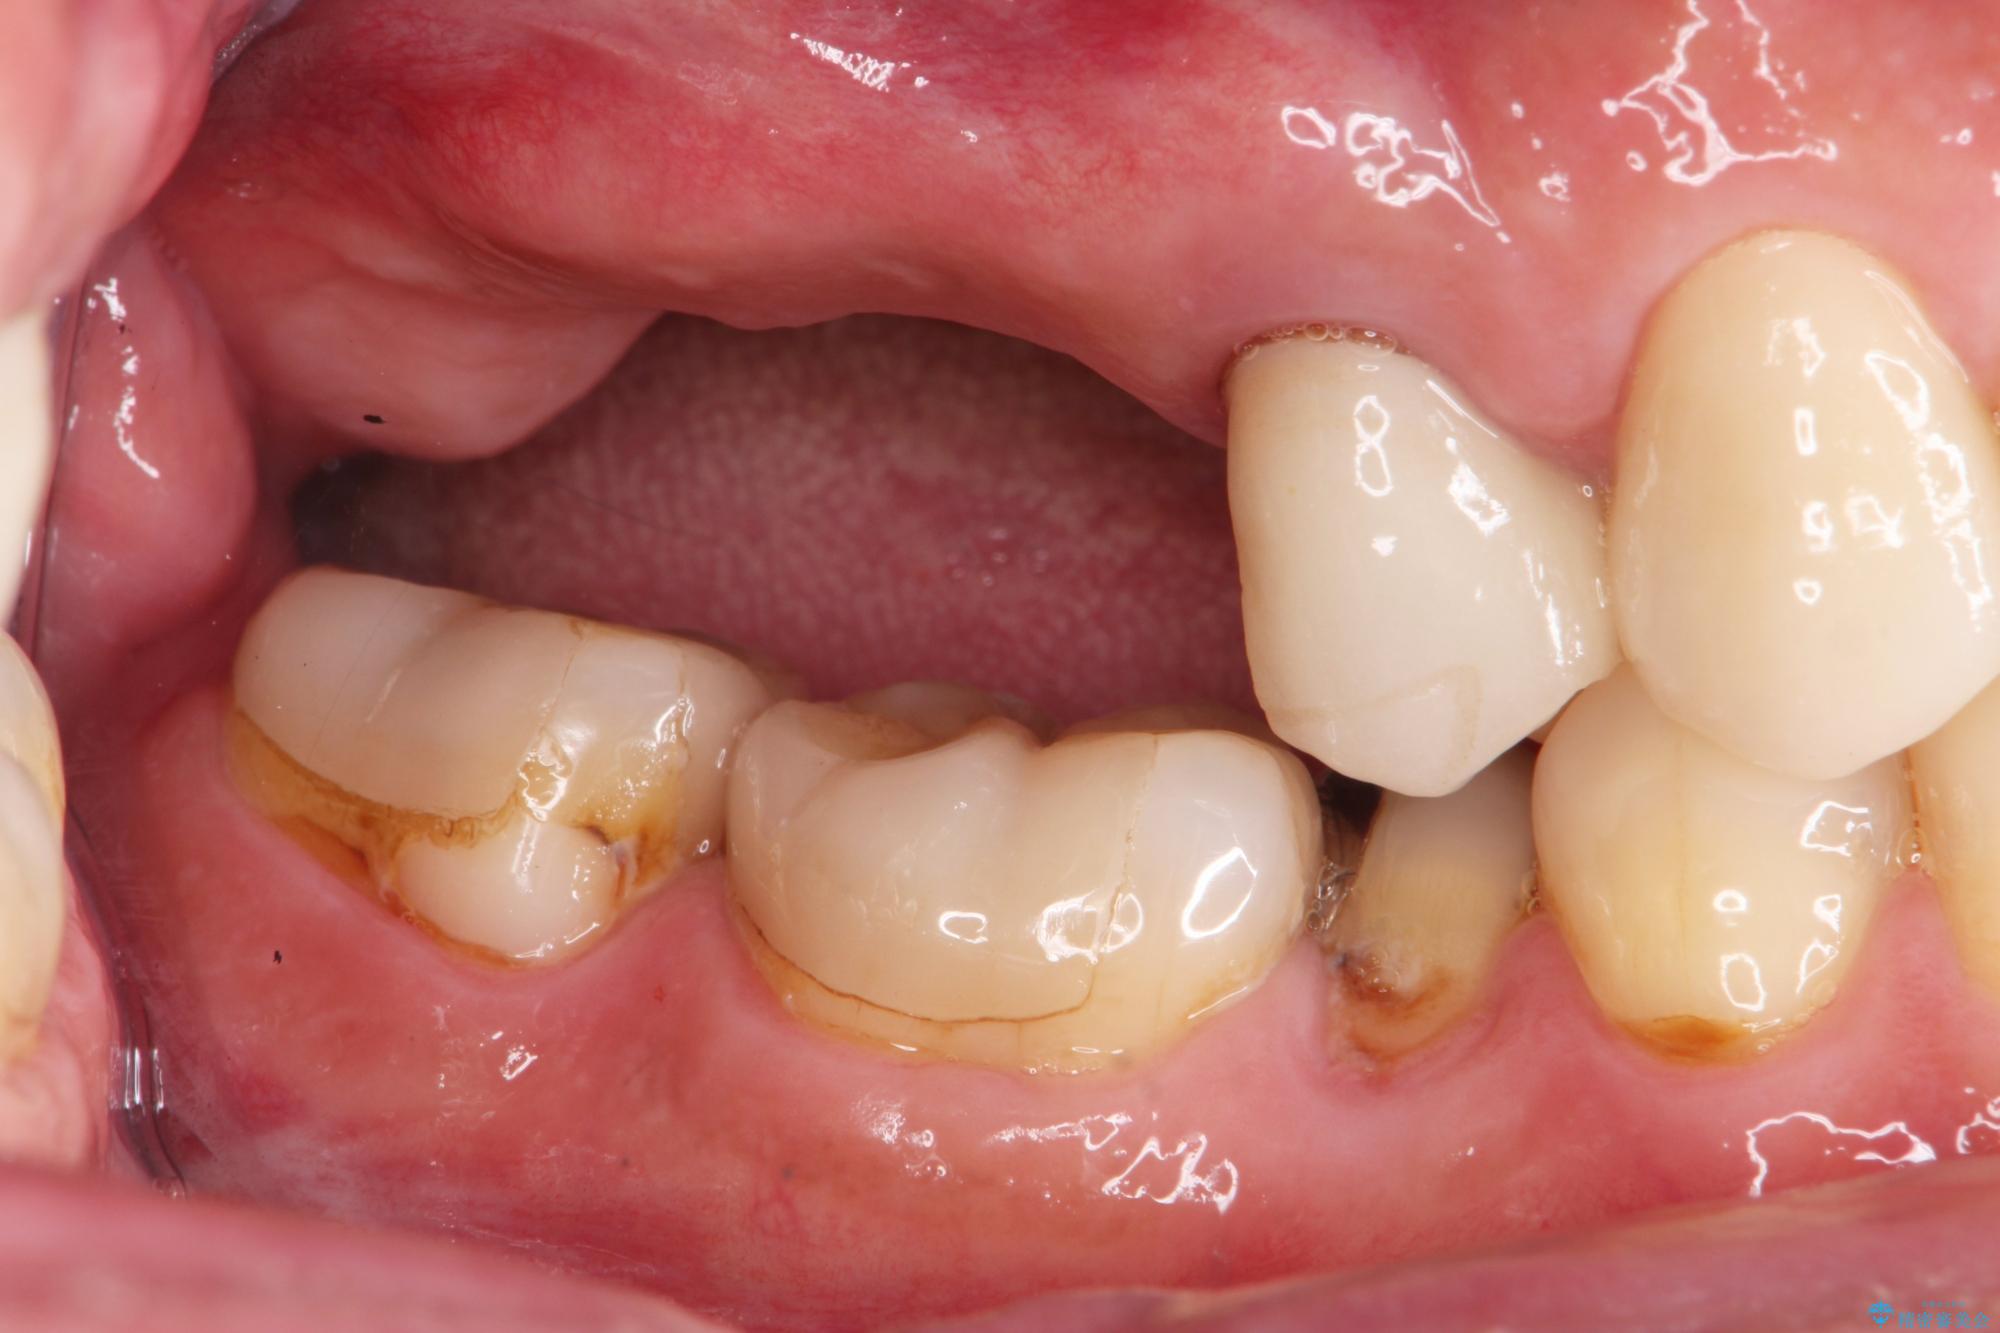

- 歯を抜いたまま放置してしまい、「やはりしっかりと噛めるような状態にしてほしい」とインプラント治療を希望され来院されました。

人工歯根であるインプラントを埋入することで奥歯でまたしっかりと噛める咬合機能を回復します。

- 88万円(インプラント×2・仮歯×2・チタンカスタムアバットメント×2・ジルコニアクラウン×2)費用は治療当時の料金となります